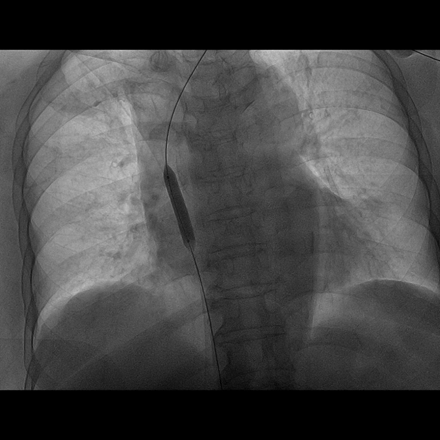

72岁钟阿姨,患尿毒症3年多,长期在我院维持性血液透析治疗,有糖尿病基础疾病,血管条件差,无法行动静脉内瘘手术建立血管通路。钟阿姨曾于2012年底在我院植入右侧颈内静脉半永久透析管,1年后因管路血流不通畅,予以行左侧颈内静脉半永久透析导管术,继续规律血液透析,近期因管路血流量不佳入我院住院治疗。入院后查CTV提示左侧颈内静脉纤细,上腔静脉怀疑血栓,右侧颈内静脉狭窄。由于考虑手术风险高,手术难度较大,肾内科严跃红主任医师邀请广州市第一人民医院放射介入科陈国东副主任医师,联合我院心血管介入科邓天明副主任医师和DSA室医护人员,术前全面评估,术中精细操作,血管造影显示:左侧锁骨下静脉、头臂静脉、上腔静脉上中段狭窄,上腔静脉下段完全闭塞,遂用三个球囊对狭窄闭塞的静脉血管进行逐级扩张成形后,上腔静脉血管复通,DSA引导下辅助半永久透析导管植入,手术成功。

球囊扩张